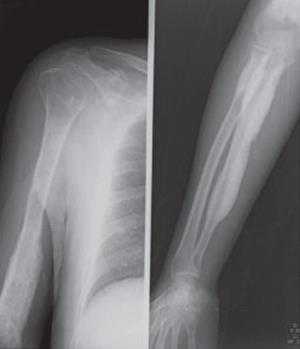

У детей младшего возраста гиперостоз в основном носит несимметричный, очаговый характер. Участки с утолщением кортикального слоя чередуются с участками, где эти изменения отсутствуют. С возрастом гиперостоз становится симметричным и приобретает генерализованный характер. Наиболее часто поражаются длинные трубчатые кости, хотя вовлечение коротких костей не является исключением. Утолщение кортикального слоя приводит к сужению костномозгового канала (рис.), но в отличие от остеопетроза (мраморной болезни) он никогда полностью не закрывается. В губчатой кости при К. — Э. б. наблюдается утолщение трабекул и грубая их структура.